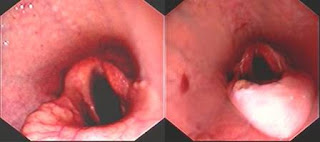

Abnormalities of the larynx visualised using endoscopy